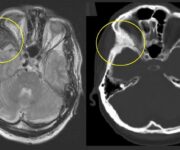

La neoformazione è radiotrasparente, a margini netti, tondeggiante o ovoidale, a volte con addensamento pericistico, può avere rapporto con i denti.

L’esame radiografico evidenzia area di radiotrasparenza delimitata da un orletto di addensamento osseo ben evidente, forma rotondeggiante e rapporto con gli elementi dentari.

Le cisti del mascellare superiore possono presentare dei problemi di diagnosi differenziale con la cisti mucosa a primitiva partenza della mucosa antrale del seno mascellare. La cisti mucosa del seno ha un margine superiore cupoliforme mentre la cisti radicolare non presenta margine netto cupoliforme ed ha doppio orletto superiore (cisti e mucosa del seno).